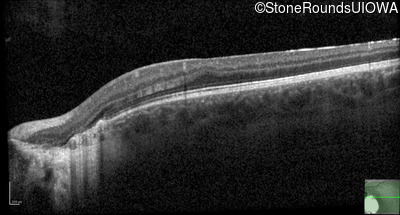

Optical Coherence Tomography - Right - 20/50

Exemplar / OCT Stack

OCT Stack